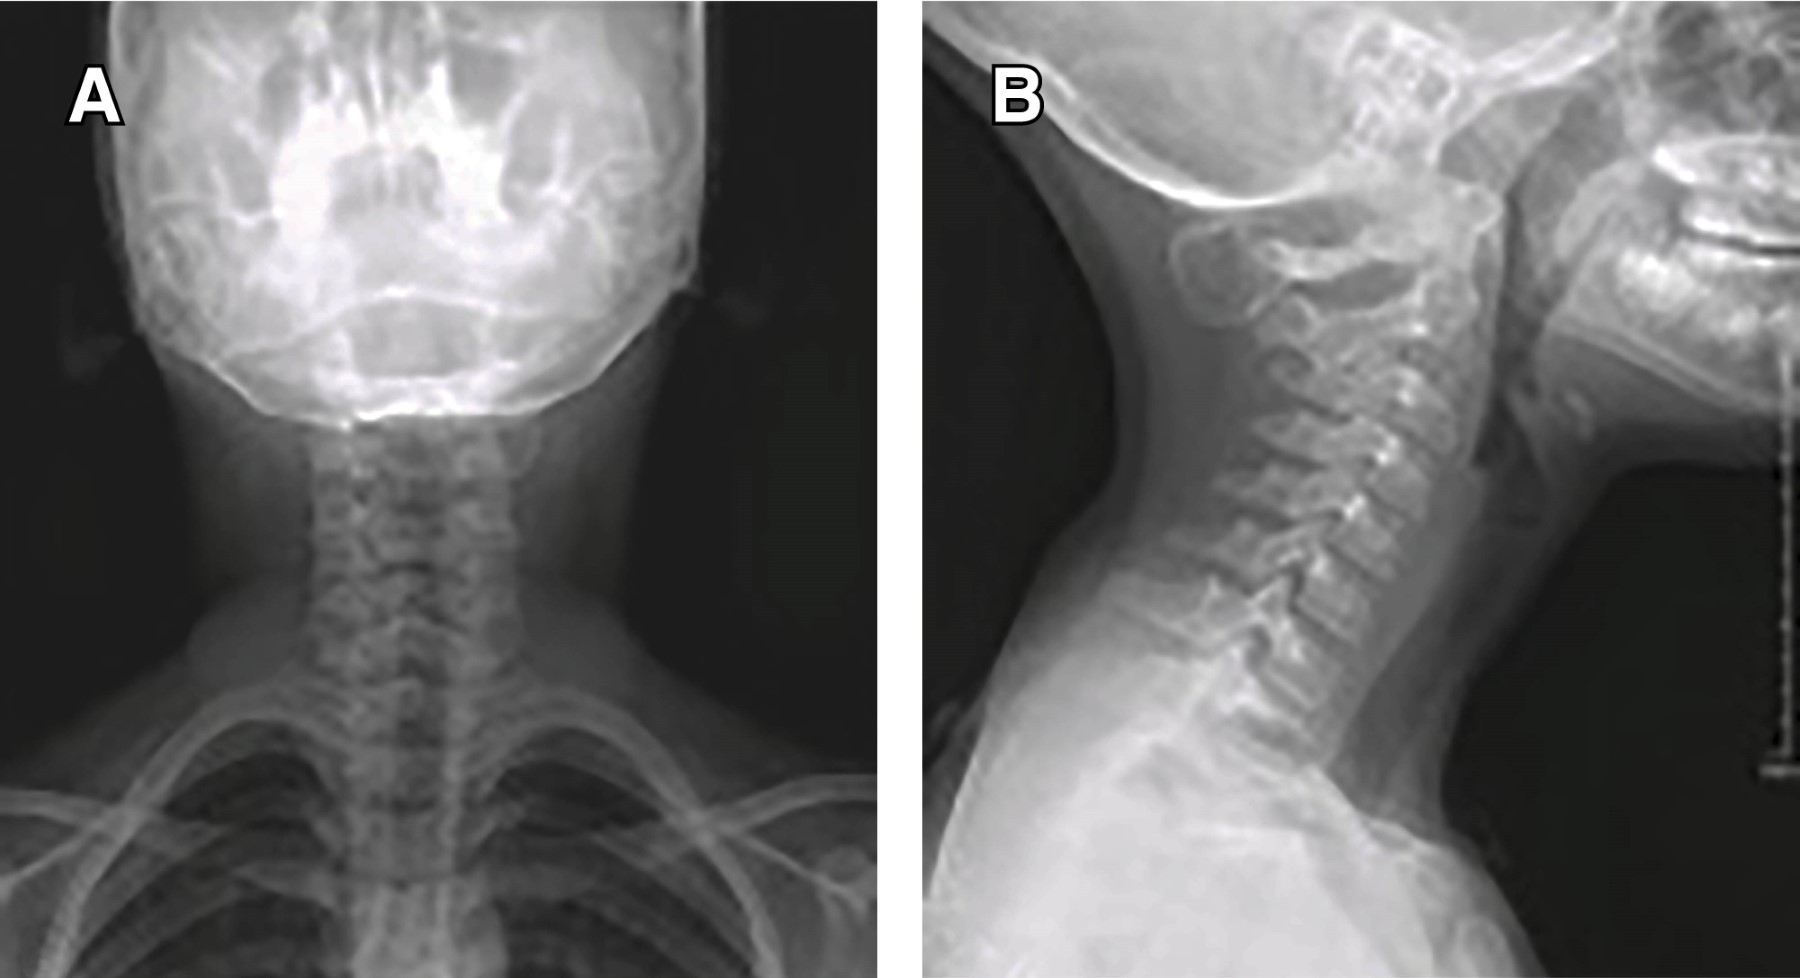

Introduction: myositis ossificans (MO) is described as a non-neoplasic heterotopic bone formation at soft tissues and muscle. It is a rare entity in children, but it must be included within the differential diagnosis of a malignant tumor or an infection. Material and methods: the objective of this retrospective study is to describe three clinical cases of circumscribed myositis ossificans; the first one is a 10-year-old girl with a post-traumatic cervical injury, the second one is an 11-year-old boy with an atraumatic-type distal thigh injury, and the third one is an 8-year-old boy with a post-traumatic right thigh tumor. Results: the diagnosis was made on the basis of the clinical presentation, radiologic imaging and histopathological findings. The results obtained by conservative treatment were good in all cases, with resolution of pain and progressive reduction in size of lesions, without registering complications during follow-up. Conclusion: myositis ossificans is a rare entity, whose diagnosis is usually complex and may require a multidisciplinary team, and whose prognosis is nevertheless favorable.

Figure 1